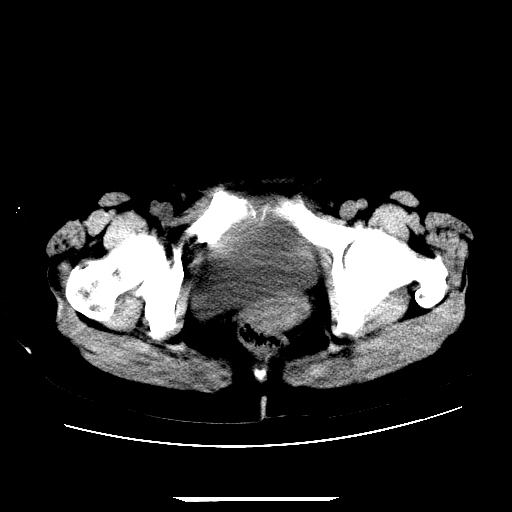

f,45y.怀孕4月晕倒,b超提示死胎,有手术结果,请展开讨论后明天告诉。

膈下-肠间隙内见气体密度影,子宫轮廓显示不清,宫腔-腹腔积液,首选考虑---子宫破裂出血。

1)宫腔妊娠。2)子宫破裂出血,腹腔及盆腔积血。

感谢同行们的高见。手术结果:子宫破裂出血。

我们的诊断是:腹、盆腔积液(考虑腹盆腔脏器破裂出血);宫腔妊娠。让人纳闷的是当时我们没有经验,现在回头看看分析:4月宫腔妊娠:1、洋膜囊不可能紧贴胎体这么小;2仔细看看子宫后壁肌层模糊不清;3腹、盆腔液体来源原因?4、45岁高龄妊娠有晕倒。由此可大胆诊断:宫腔妊娠子宫破裂出血。